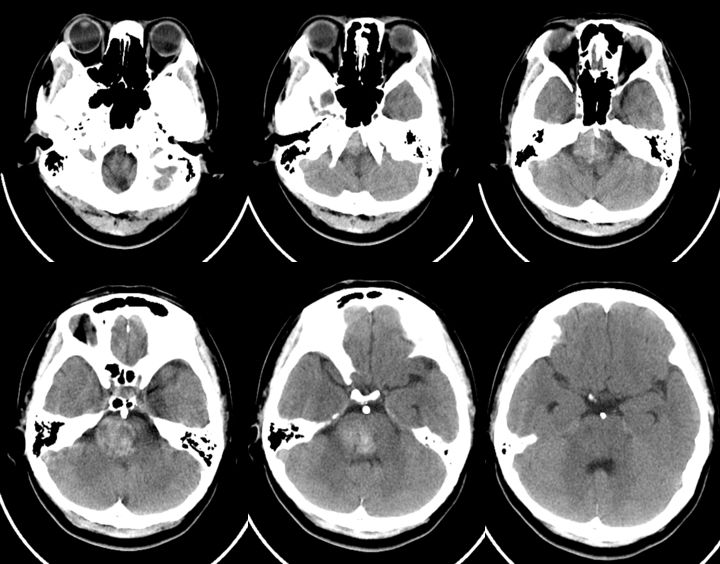

当地医院头CT:右侧脑干占位(2019-09-06)(图1)。

图1

5、术后患者恢复良好,复查CT与术前无明显改变。查体:神志清,精神可,双侧瞳孔等大等圆,复视、吞咽困难、饮水呛咳较入院时明显改善,右侧肢体肌力5级,左侧肢体肌力4级,四肢肌张力正常,双侧病理征阴性(图12)。

图12